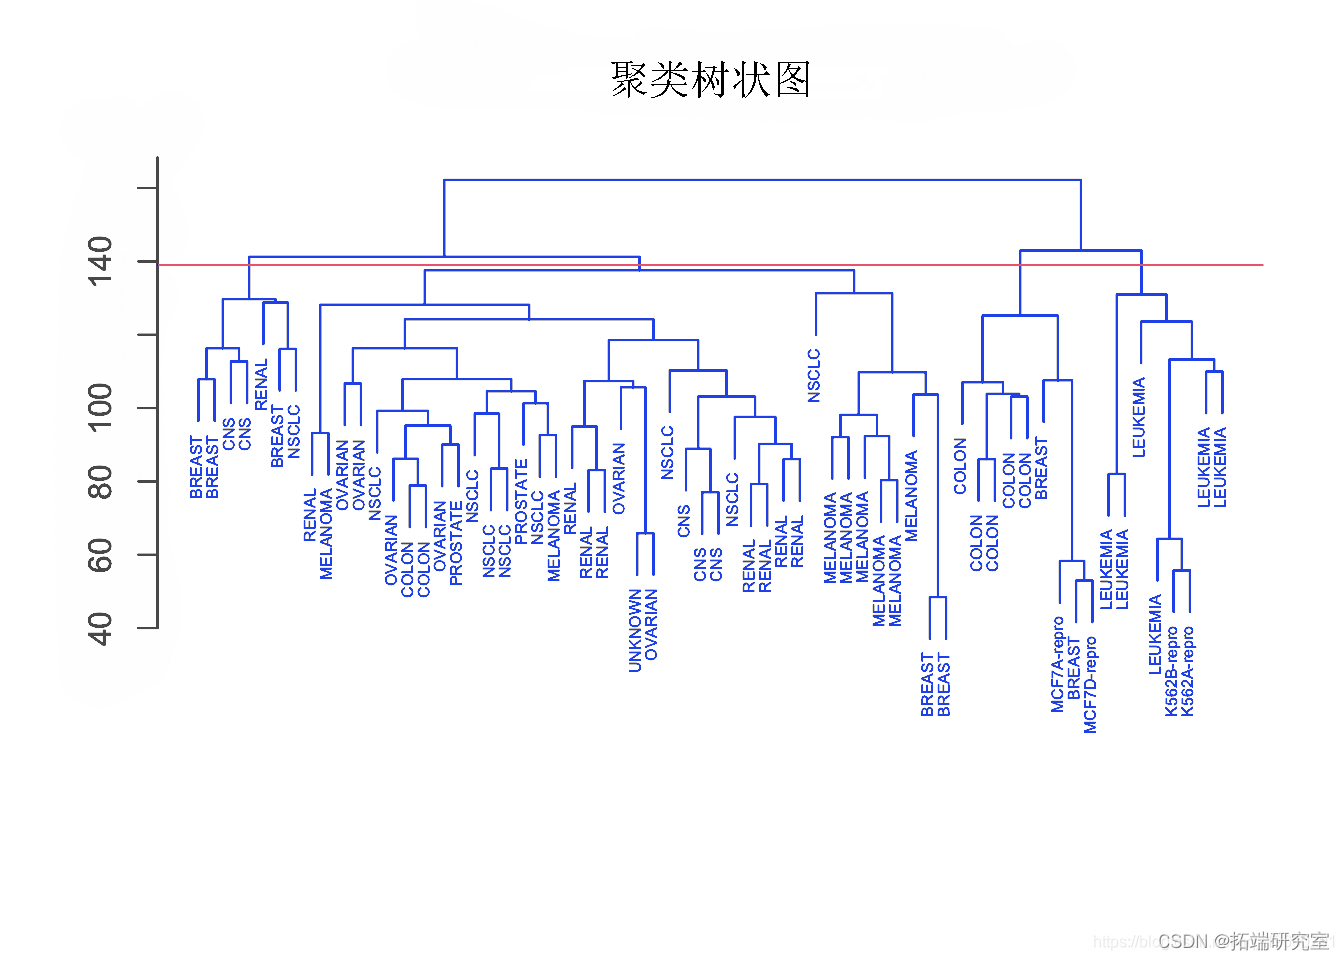

plot(hclust,ylab = "",cex=".5",col="blue") #使用全链接对观察结果进行层次聚类。

plot(hclust,cex=".5",col="blue") #使用平均链接对观察进行层次聚类。

par(mfrow=c(1,1))

plot(hclust,col="blue") #使用单链接对观察进行层次聚类。

观察结果

单链接聚类倾向于产生拖尾的聚类:非常大的聚类,单个观测值一个接一个地附在其中。

另一方面,全链接和平均链接往往会产生更加平衡和有吸引力的聚类。

由于这个原因,全链接和平均链接比单链接层次聚类更受欢迎。单一癌症类型中的细胞系确实倾向于聚在一起,尽管聚类并不完美。

plot(hcu)

abline

参数 h=139 在高度 139 处绘制一条水平线。这是 4 个不同聚类的划分结果。